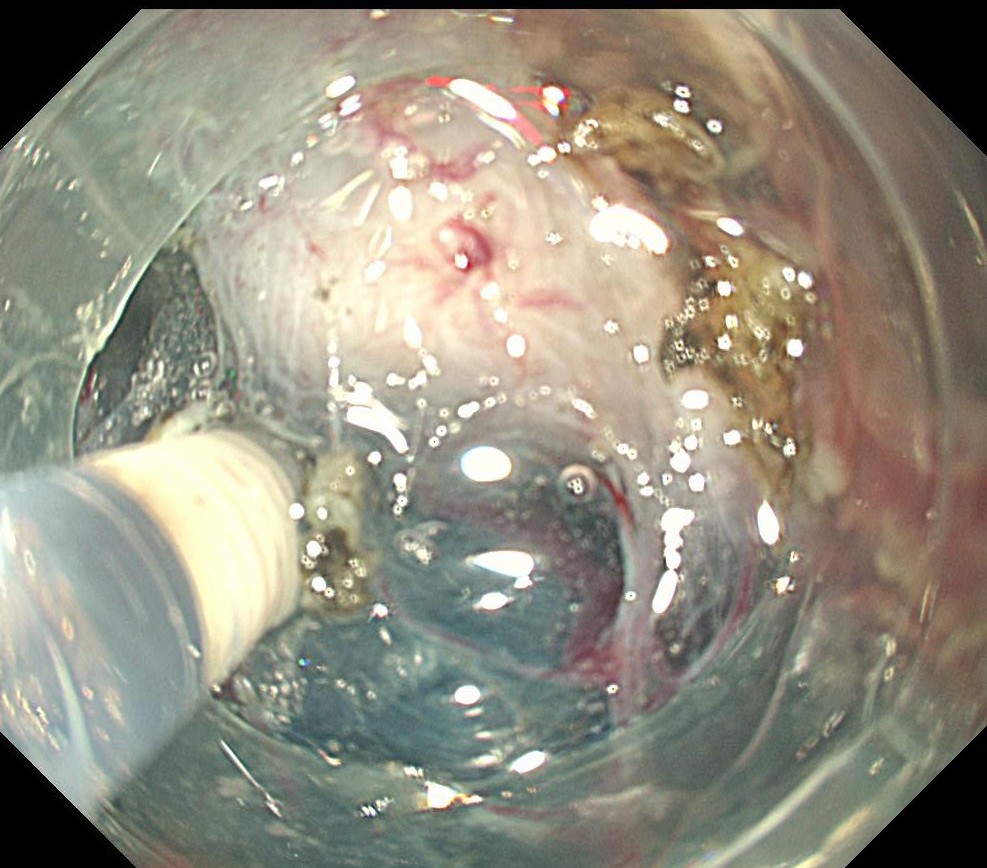

フラッシュナイフを用いて全周切開します。粘膜下の局注は生理食塩水のみを使用しています。

粘膜下層剥離術を開始します。

フラッシュナイフで剥離をすすめます。VIO300のスイフトコアグレーションモードを使用しています。